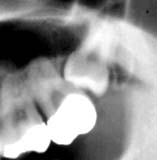

35歳 男性 「8 拡大

初診時 パノラマ 「8 歯冠カット後抜歯中止

口腔内全体に縁下歯石の沈着が著しくカリエスも随所に認められた。 左側の頬および「8部の歯肉腫脹は著しく、開口しにくい状態であったため口腔内からは状況を 把握するのが困難な状態であった。X線所見により、「8歯冠の一部がカットされた水平埋伏歯を 確認。

歯石を除去したのち、浸潤麻酔下において埋伏歯を抜去(所用時間:15分)。 翌日多少の腫脹が認められたものの経過は良好。

抜歯を中断したケースの多くが、歯肉の剥離不足のように思われます。切開面積が大きくなれば 痛みも大きくなると思われがちですが、実際には切開面積と術後の痛みは比例しないようです。 ましてや、切開面積が狭く手術野が見えない状況でやむなく抜歯を中断して無用の疼痛を引き起こす よりは大きく切って確実に抜く必要があるのではないでしょうか。 手術野の明視は外科の基本。

技量の違いもありますので、歯が抜けなかったことは致し方ないとしても、あとの処置が まずいのでは? 露髄の状態まで歯冠カットして放置すれば激痛を招くのは必至です。 大学病院とか、しかるべき施設に紹介して早急な処置をこうずるべきではないでしょうか?